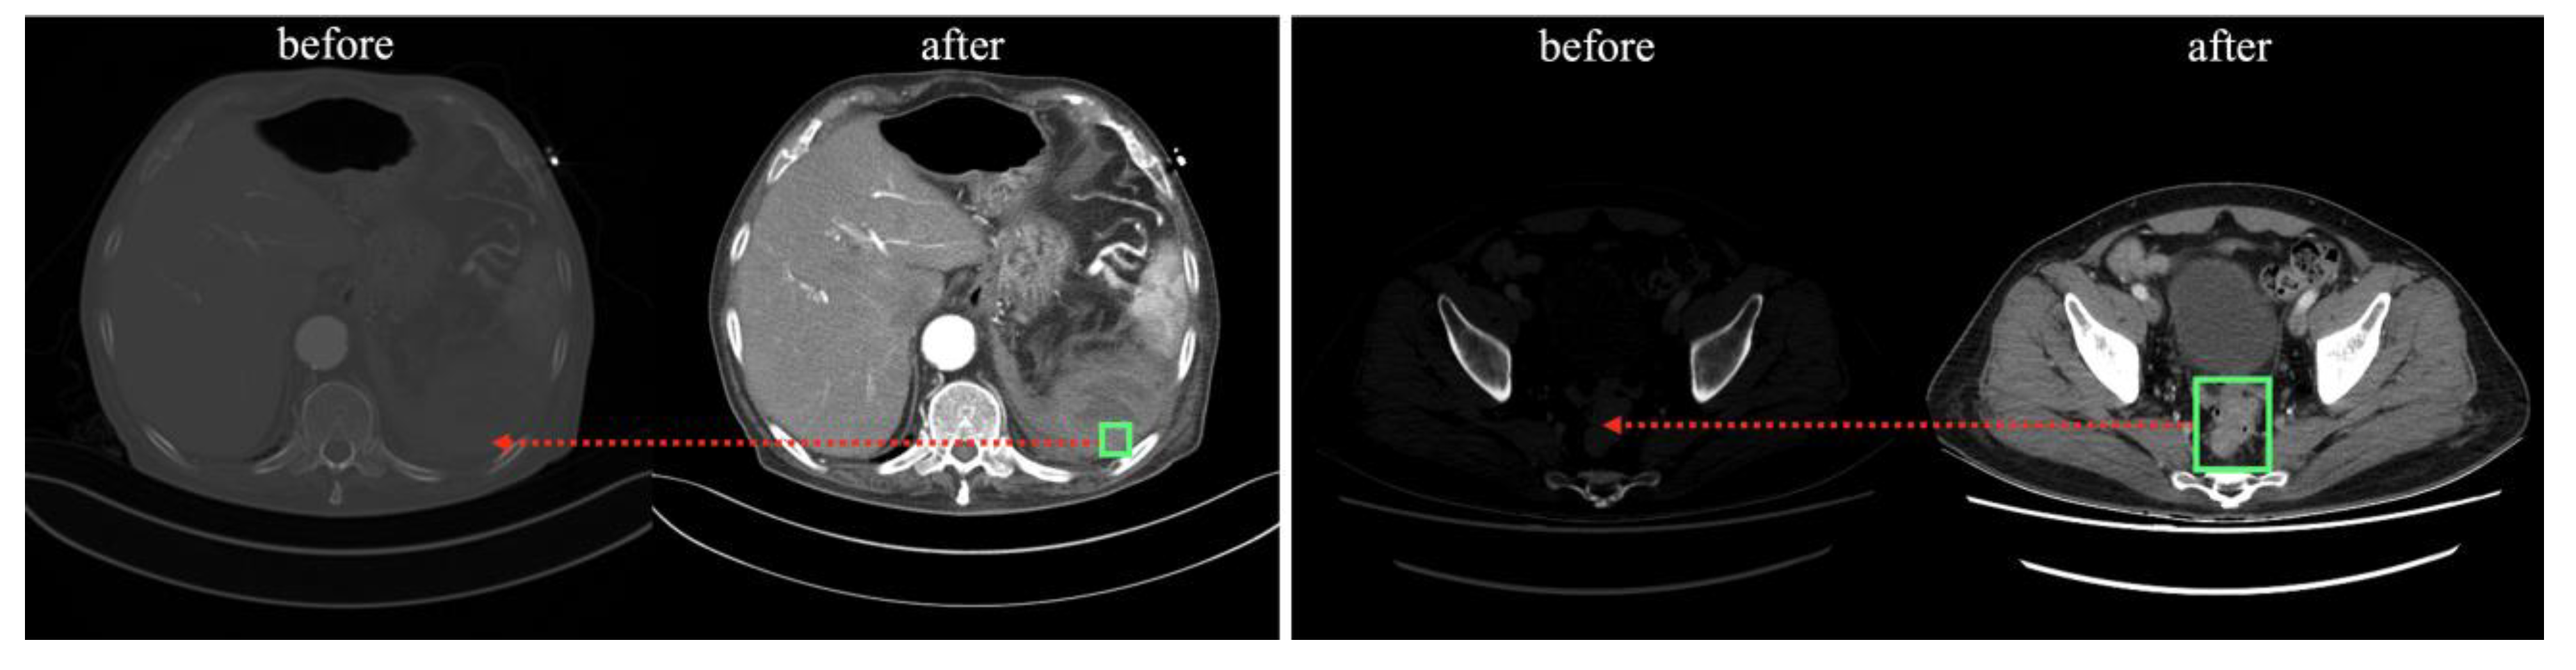

The processed images were normalized so that each pixel was linearly stretched by fitting a value between 0 and 1, and stored as a 512 × 512 pixel NumPy format array. The location of the lesion (green box) and structures, such as various organs in the abdomen are more visually distinct (red arrows) compared with the pre-processed images in Figure 2.

Figure 2.

Comparison of before and after processing of DICOM file.